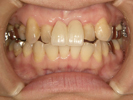

30代女性

事故のため、前歯を2本失いました。

インプラントと矯正治療をしました。

| 治療前 | ||

| インプラント後、仮歯を入れました。 | ||

| 矯正設置を着用し、歯列矯正を行いました。 | ||

| 治療後 | ||